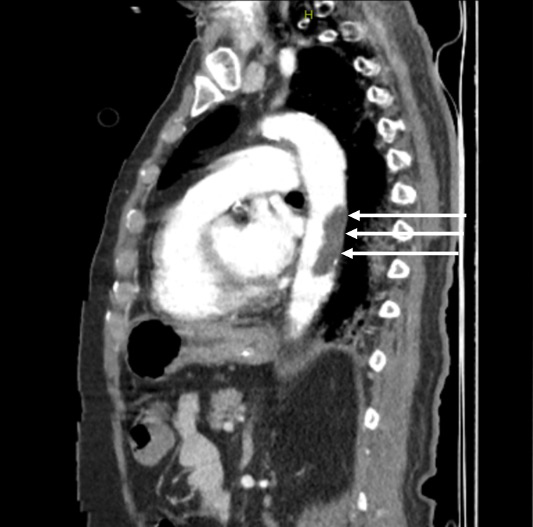

On the 13th day, the left foot was noted to be cold and ischemic, with the posterior tibial pulse not palpable. Similarly, the left hand was cold, and the radial pulse was absent. Arterial thrombosis was suspected, and Doppler ultrasonography confirmed thrombosis in the posterior tibial artery. A contrast-enhanced CT angiogram (Figure 1-3) revealed arterial thrombosis extending downward from the descending aorta, a splenic subcapsular ischemic appearance, arterial thrombosis narrowing the lumen in the left iliac and femoral arteries, and posterior tibial artery occlusion in the left leg. The patient was managed medically without surgical intervention, pentoxifylline 1500 mg/24 h infusion, dipyridamole 75 mg 1x1 tablet was started, and enoxaparin was increased to 60 mg twice daily.